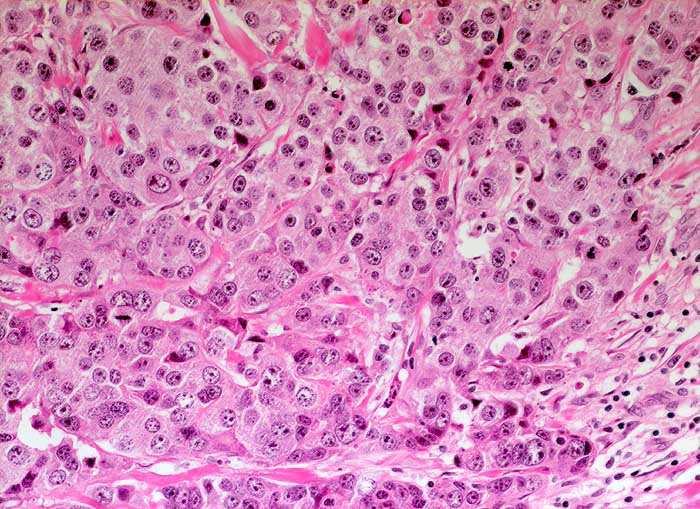

Wenig differenziertes invasiv duktales Mammakarzinom

Trabekulär angeordnete stark atypische Tumorzellen mit deutlicher Pleomorphie und hyperchromatischen Kernen. Reichlich eosinophiles Zytoplasma.

Sonographisch wachsender Befund unklarer Dignität im oberen äusseren Quadranten rechts.

Histologie

Vergrösserung

200